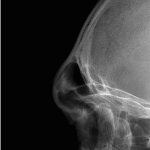

Otoplasty Reversal with ePTFE Postauricular Wedge Case Example

Reverse otoplasty refers to partially or fully undoing an overcorrected ear-pinning surgery so the ear sits a bit farther from the head again. While an overcorrected car from otoplasty surgery is ultimately determined by the patient there are some measurable guidelines for the natural angulation of the ear from the side of the head (auriculocephalic angle) When Read More…